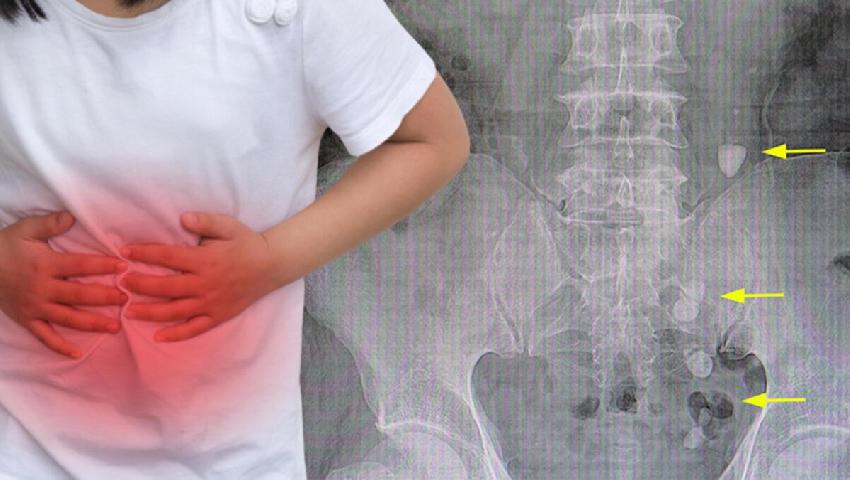

ABD’li uzmanlar artan sıcaklıların böbrek taşlarında artışa neden olacağı sonucuna ulaştı.

İki iklim senaryosu belirleyen Philadelphia Çocuk Hastanesi’nde görev alan bilim insanları 2100 yılına kadar ortalama sıcaklığın 2,3 derece artması durumunda böbrek taşı olan kişi sayısının yüzde 2,2 artacağı sonucuna ulaştı.

3.6 derecelik artışa ev sahipliği yapan ikinci senaryoda ise böbrek taşı olan kişi sayısının yaklaşık yüzde 4 artacağı belirlendi.

Konsantre idrar, kalsiyum, oksalat, fosfatlar ve ürik asidin kristalize olması ve böylece taş oluşturması için ideal bir ortamın oluşmasına neden oluyor.